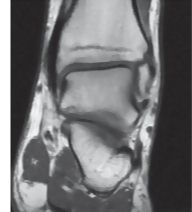

Coronal T1 MRI Through the Ankle Joint